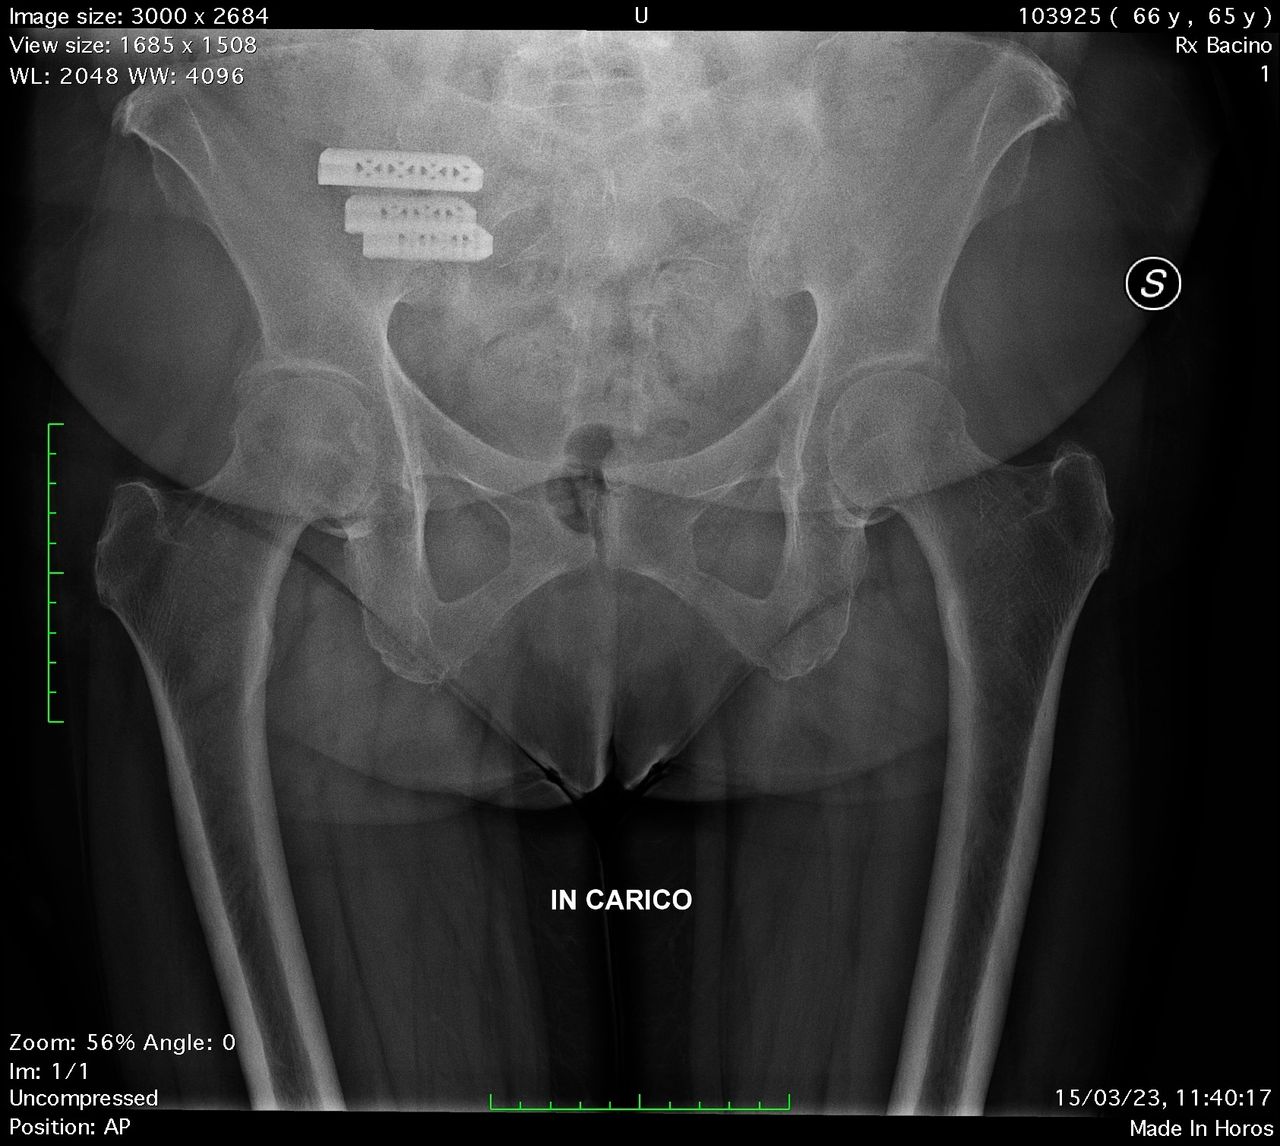

Una causa poco studiata, ma di grande interesse, è l’infiammazione dell’articolazione Sacroiliaca. Questa articolazione, che connette la nostra colonna alle gambe, agisce come un ammortizzatore per i carichi che ogni giorno gravano sul nostro corpo.

Si stima che circa il 30% dei pazienti con mal di schiena abbia una infiammazione Sacroiliaca, ma questo numero sale al 75% nei casi di pazienti sottoposti ad artrosi lombare chirurgica.

La diagnosi viene effettuata tramite manovre cliniche e da successive infiltrazioni all’interno dell’articolazione.

Infiltrazioni, denervazioni ed esercizi specifici per il rinforzo della muscolatura adiacente all’articolazione Sacroiliaca sono spesso in grado di risolvere il problema.

In caso di non risoluzione, è possibile intervenire chirurgicamente con una procedura percutanea mini invasiva, in grado di unire chirurgicamente i due capi articolari, risolvendo il mal di schiena.

La degenza è generalmente di 1-2 giorni e il paziente riprende a camminare immediatamente dopo l’intervento, con un carico parziale per 10-15 giorni.